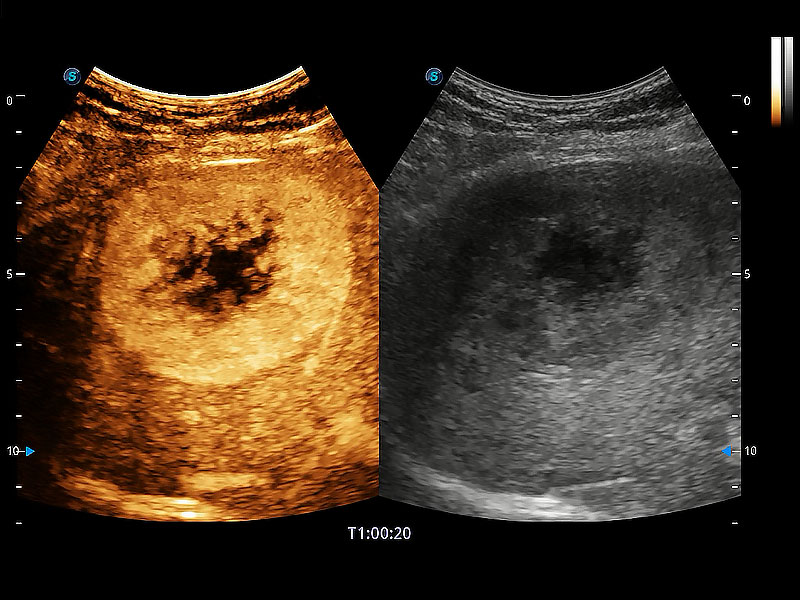

极大提升超低速微细血流的检出能力,同时更精准地滤除软组织和超声信号,为兽用医生提供以往无法通过常规血流获得的疾病诊断信息。

在传统二维血流成像的基础上,呈现血流的立体感,具有动感的生命力之美。即便是微小的血管也能轻松应对,提高了血流的视觉敏感性。

操作简便,无需高频度外力作用即可真实反映组织的形变,快速评估肿瘤良恶性。

非线性融合造影成像充分利用谐波和基波信号,为难以观察的血流进行增强显像。可用于线阵、凸阵、微凸阵、相控阵探头。